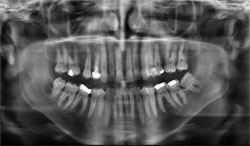

Digital Imaging Galway – OrthoPantoGram

OrthoPantoGram is a Digital OPG – a two dimensional image which gives an excellent overview of the teeth, the supporting bone and areas of bone loss, the presence of any root canal treatments, and many pathologies which might need further investigation.

We may take this X-ray initially to give an overview of your dentition and structures of the jaws to assess which areas may need investigation.